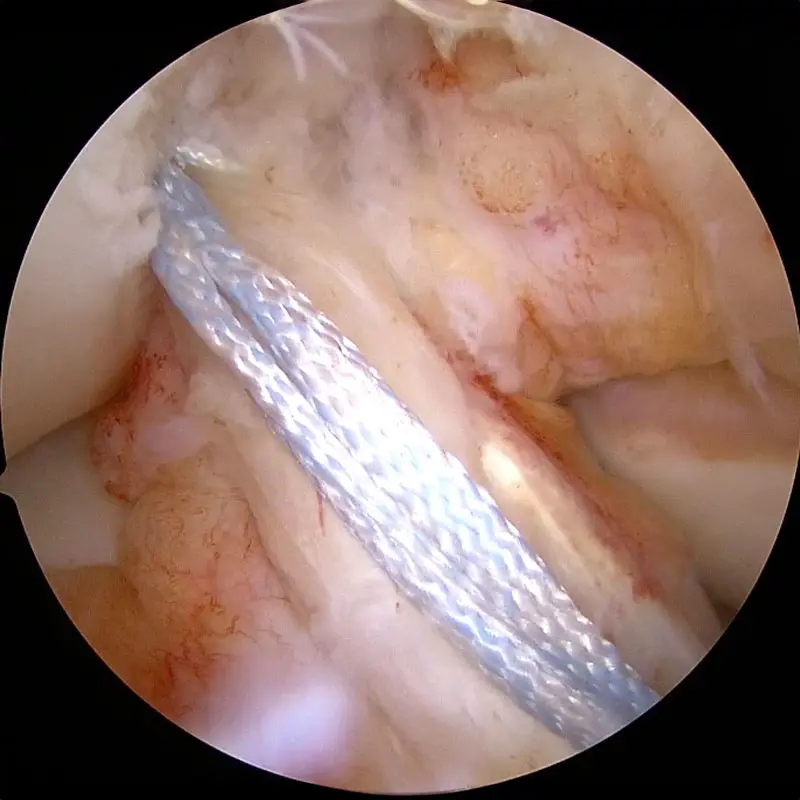

Stitches woven through ACL stump.